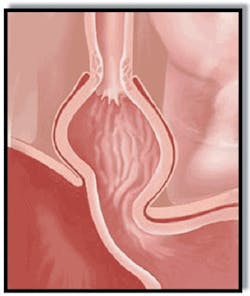

Another well-described condition associated with GERD is hiatal hernia (Figure 5). It is defined as the protrusion of the upper part of the stomach above the diaphragm (a thin, dome-shaped muscle that separates the thoracic cavity (lungs and heart) from the abdominal cavity (intestines, stomach, liver, etc.)). (See Figure 6)

- Normally, the diaphragm acts as an additional barrier, helping the lower esophageal sphincter keep acid from backing up into the esophagus.

- A hiatal hernia distorts the lower esophageal sphincter, impairing its function and making it easier for the acid to back up.

- Hiatal hernias can be caused by persistent coughing, vomiting, straining, or sudden physical exertion. Obesity and pregnancy can make the condition worse.

- Hiatal hernias are very common in people older than 50.

- Hiatal hernia usually requires no treatment. In rare cases when the hernia becomes twisted or is making GERD worse, surgery may be required.